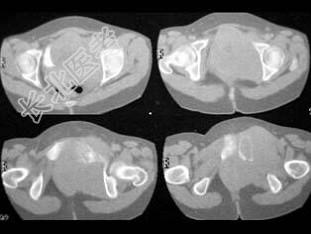

- 单项选择题女,54岁, 因反复左髋、左下肢痛伴左下肢活动障碍约半年,结合所提供的图像, 最可能的诊断是 ( )

A、骨髓瘤

B、滑膜肉瘤

C、骨转移瘤

D、尤文肉瘤

E、骨巨细胞瘤